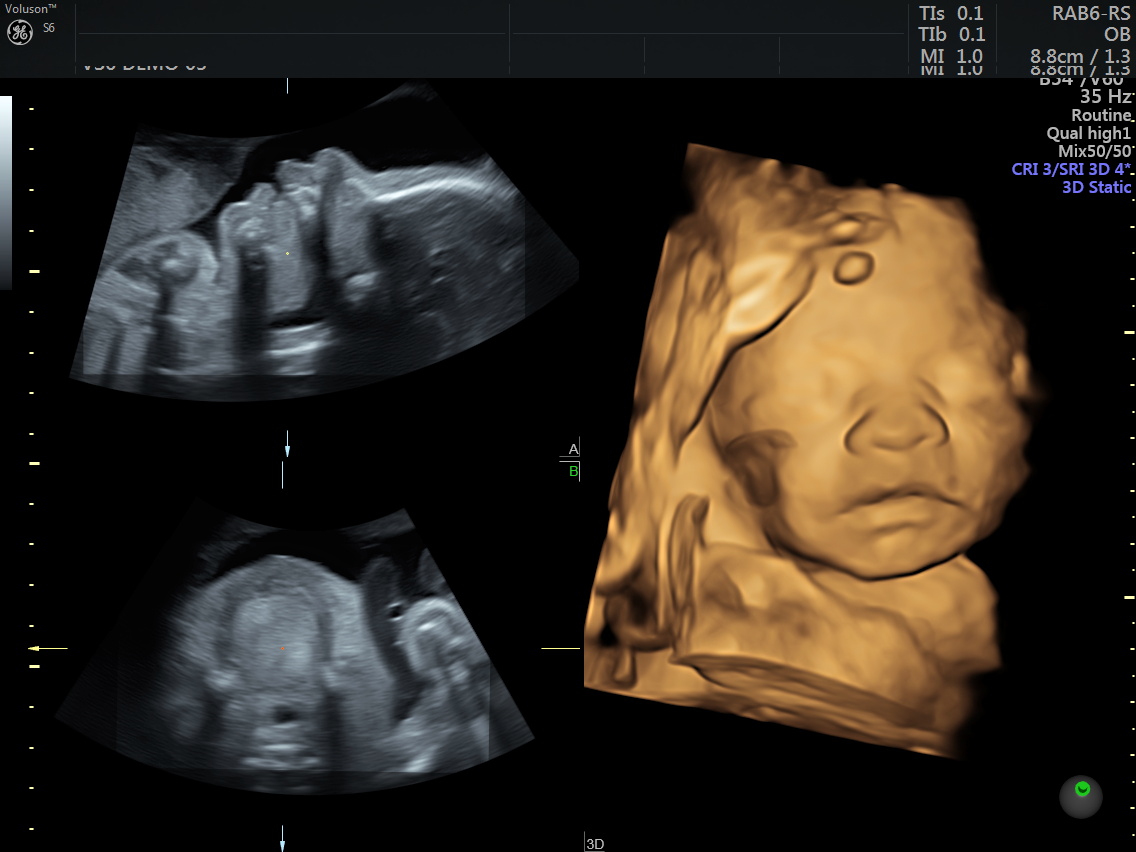

4D (dört boyutlu), Renkli, Ayrıntılı Gebelik Ultrasonu

4 boyutlu renkli ultrason ve 3 boyutlu ultrason aslında aynı anlama gelmemesine rağmen halk arasında , ayrıntılı ultrason, detaylı ultrason , ileri düzey ultrason, anomali ultrasonu , 2. basamak ultrason, ikinci düzey ultrason, renkli ultrason , büyük ultrason , genetik ultrason ile aynı anlamda kullanılmaktadır.

4 boyutlu renkli ultrason cihazı ile çok erken dönemde cinsiyet, yarık dudak, yarık damak, eksik parmak, beyin ve omurilikten kaynaklanan rahatsızlıkların erken tanısı konulabiliyor.